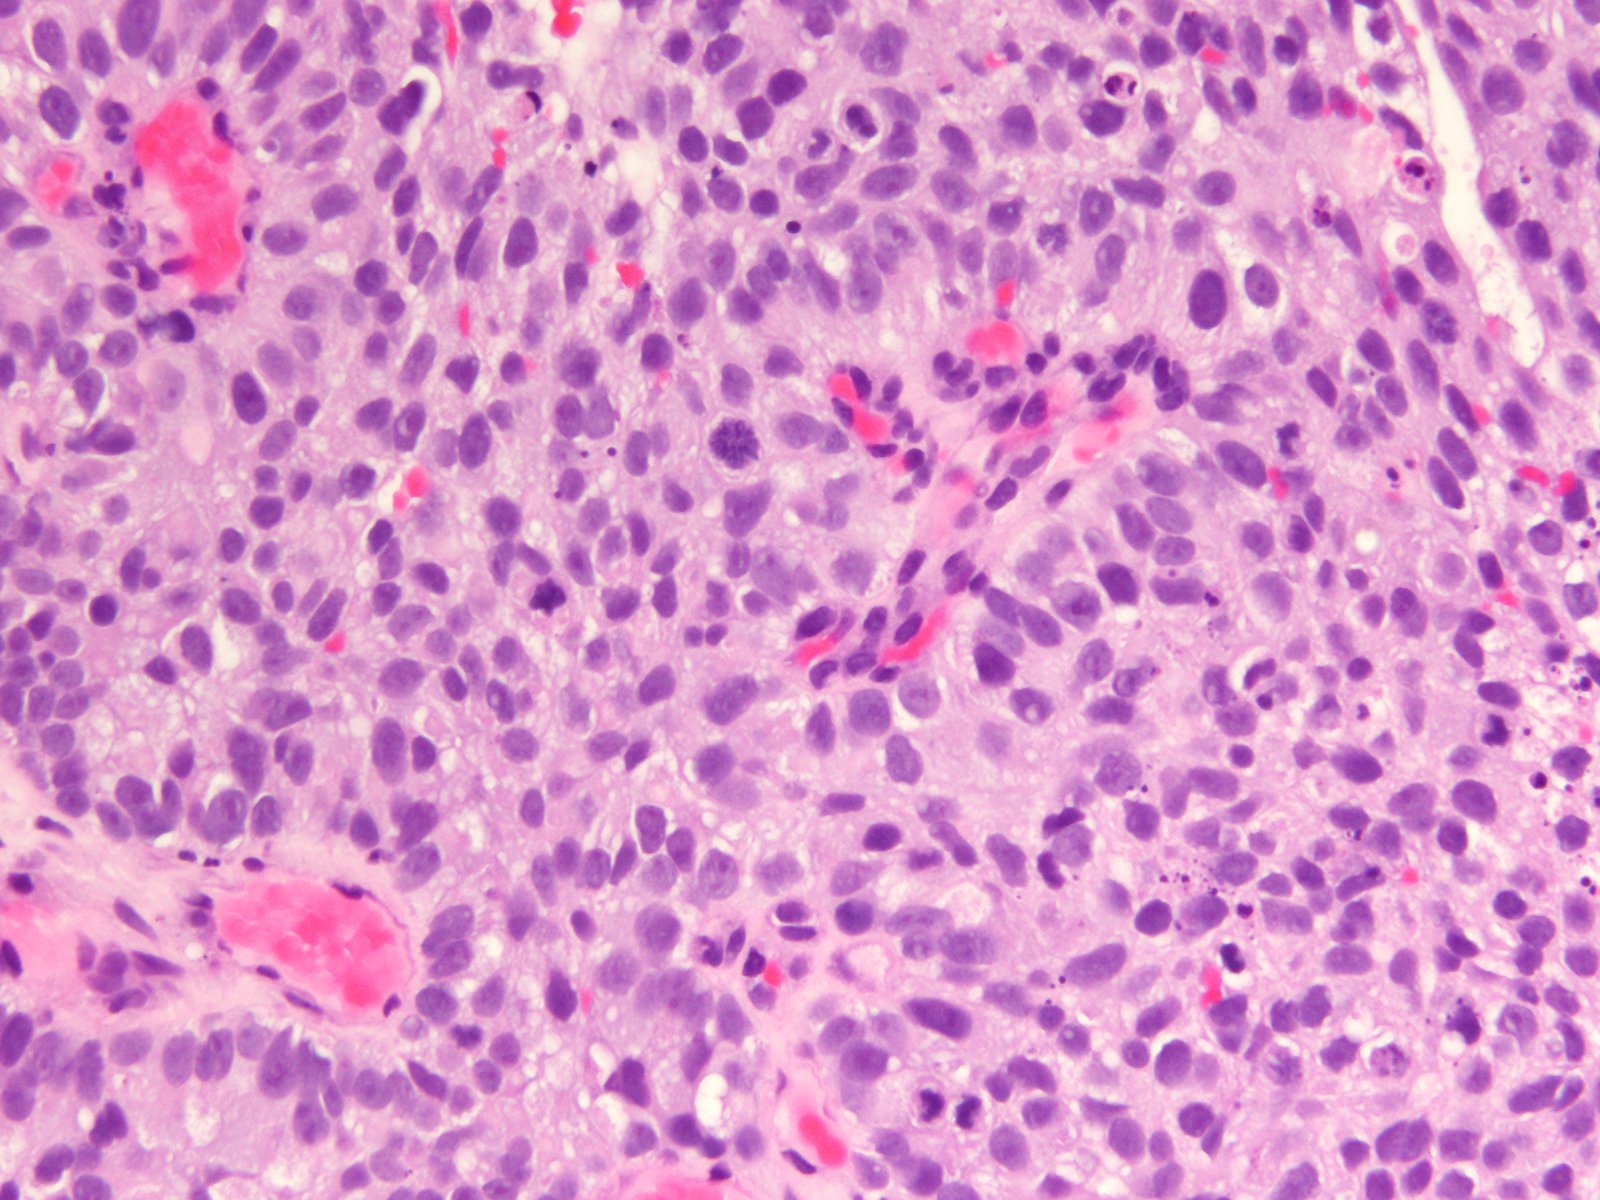

Bladder Papillary Lesions

Case ID: 565

Papilloma

PUNLMP

Low-grade papillary urothelial carcinoma (LG-PUC)

High-grade papillary urothelial carcinoma (HG-PUC)